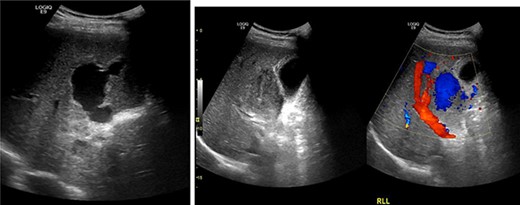

Resuscitation was carried on with 2 l of normal saline and two PRBC units to stabilize the patient. The computed tomography (CT) scan identified Grade 4 liver injury with hemoperitoneum (Fig. 2). Subsequently, the multiple bone fractures underwent surgical fixation, and post-operatively, he was hemodynamically stable. On the fifth day after admission, repeated CT scan demonstrated the liver injury with no evidence of hepatic pseudoaneurysm (Fig. 3). The patient remained stable with tolerated feeding with no abdominal pain or distension. On the Day 17, he developed abdominal pain mainly in the epigastrium, which was associated with nausea and deep epigastric tenderness. Abdominal ultrasound (US) (Fig. 4) and CT scan (Fig. 5) revealed complex, large intraparenchymal hepatic pseudoaneurysm (measuring about 58 × 41 × 30 mm) related to the left hepatic artery Segment 4 branch with surrounding hematoma located mainly at segment 4B/A ,and there was another tiny pseudoaneurysm seen at Segment 4A. Selective angiography confirmed the diagnosis of pseudoaneurysm with multiple blood supplies from Segment IV and Segment II.

Contrast-enhanced CT scan revealing a right hepatic artery pseudoaneurysm in the right lobe of the liver.